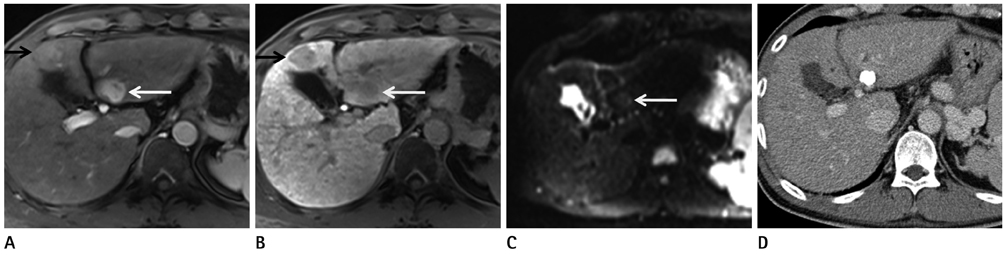

To compare diffusion-weighted imaging (DWI) and gadoxetic acid-enhanced (Gdx) magnetic resonance imaging (MRI), whether alone or in combination, for the detection of hepatocellular carcinoma (HCC) by using 3 T.

84 HCCs in 66 patients (57 men, 9 women; mean age 69.2 years) were examined using 3 T MRI. DWI (b values 0, 50, and 800 sec/mm2) and dynamic gadoxetic acid-enhanced MRI as well as hepatobiliary phase were performed. Images were retrospectively reviewed by two radiologists to compare the diagnostic performances of DWI and Gdx MRI alone and in combination for the detection of HCC. Alternative free response receiver operating characteristic analysis and comparison of sensitivities were used for statistical analysis.

The sensitivity of Gdx set (73/84, 87%) was significantly higher than that of DWI set (60.5/84, 72%) for both observers. The Az values of DWI and Gdx MRI for the detection of HCC were not statistically significant for either observer (Az for DWI = 0.818 and 0.864, Az for Gdx MR = 0.902 and 0.842, respectively, p = 0.107 for observer 1 and p = 0.738 for observer 2). The combination of both techniques did not increase the sensitivities of detecting HCC in either observer. When lesions smaller than 2 cm were considered, the DWI set yielded a significantly lower sensitivity as compared with either the Gdx set alone or the combination set.

Gadoxetic acid-enhanced MRI was better than DWI for detection the HCC by using 3 T MRI. The combination of DWI and Gdx MRI did not contribute to the successful detection of HCC.

Figure